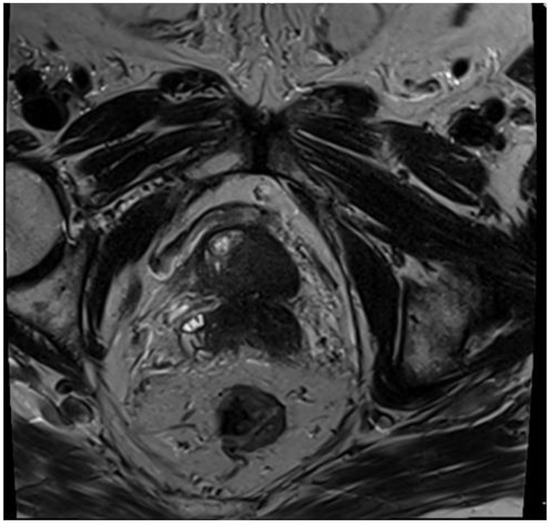

Given the persistent re-accumulation of pleural effusion and suspicious nodular pleural thickening, a diagnostic video-assisted thoracoscopic surgery (VATS) was performed. Approximately 900 mL of bloody fluid was drained, and multiple pleural nodules were biopsied. Histopathology revealed metastatic carcinoma. Immunohistochemical staining demonstrated positivity for androgen receptor (AR), alpha-methylacyl-CoA racemase (AMACR), and focal Prostein, alongside negativity for TTF1, CK20, WT1, D2-40, PAX8, GATA3, and CDX2, consistent with a primary prostatic origin [8]. Figure 4 Digital rectal examination (DRE) revealed a firm prostate gland with bilateral palpable nodules consistent with clinical stage T2c disease. Although the patient’s serum PSA was only 2.91 ng/mL, a subsequent prostate MRI revealed a PIRADS 5 lesion invading bilateral seminal vesicles Figure 5, Figure 6 and Figure 7, and a transrectal fusion biopsy confirmed ISUP grade group five disease (Gleason 4 + 5 = 9). Figure 8 A bone scan showed no skeletal metastases, and a contrast-enhanced CT of the abdomen found no evidence of abdominal metastatic disease (notable findings included multiple simple hepatic and renal cysts, and a homogeneous left adrenal adenoma). The patient was staged as cT3bN0M1 (pleural metastasis) and started on androgen deprivation therapy with bicalutamide plus leuprolide, followed shortly by abiraterone and low-dose corticosteroids. Three-month follow-up imaging demonstrated stable pleural disease and partial symptomatic relief in his respiratory complaints.

Figure 5. MR T2 weighted-images—axial plane, extensive infiltration of the gland with involvement of the seminal vesicles—T3b.